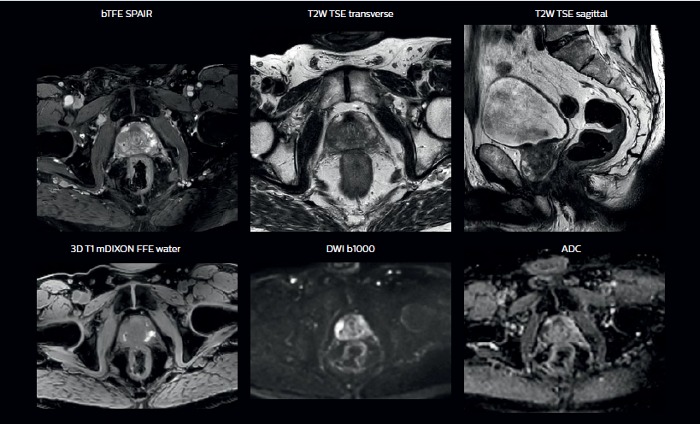

With its exceptional soft-tissue visualization capabilities and wide range of image contrasts, MRI has become a powerful tool to help more precisely define tumor boundaries. This is particularly important as it has been established that there is a high degree of uncertainty in target volume delineation, and it is even reported to represent the largest uncertainty in the entire radiotherapy process for most tumor sites**. Better visualization of the target area and nearby organs-at-risk is a key factor in enhancing target volume delineation. MRI’s expanding role also can be attributed to its functional imaging capabilities, which can inform both target characterization and treatment response.

With its superior soft tissue contrast compared to CT, MRI offers exquisite visualization of tumor boundaries and proximity to nearby critical structures.

The ability to tune contrasts can provide even more valuable information about tumor characteristics and tumor extent to facilitate enhanced delineation, and also provides possibilities for dose boosting strategies.

In addition to anatomical imaging, MRI offers the ability to obtain functional information that is beneficial for tumor detection and delineation, and for response monitoring.

Diffusion-weighted imaging (DWI) for example depicts areas of high signal intensity in soft tissues that are indicative of the restricted water mobility (i.e., diffusion) of a tumor and can also be used to identify lymph nodes. Changes in the tissue’s or lesion’s apparent diffusion coefficient (ADC) can provide insights that help predict the tumor’s response to radiotherapy.